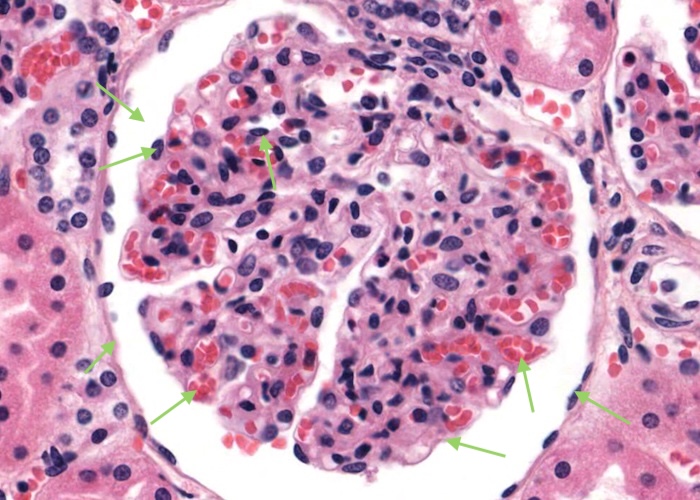

A renal corpuscle is located in the cortex and is the specialised structure where filtration occurs. Each is an aggregation of capillaries enclosed within a cup-shaped capsule called the glomerular (Bowman’s) capsule. Identify red blood cells within these capillaries. The capsule has an outer (parietal) surface layer of squamous epithelial cells and the inner (visceral) layer invests the glomerular capillaries.

The space between the glomerular capillaries and the parietal layer of Bowman’s capsule is referred to as the capsular or urinary space. This space receives plasma fluid that filters through the glomerular capillaries and the visceral layer of epithelial cells called podocytes.

In this H&E section, podocytes are difficult to distinguish from other populations of cells present (e.g. mesangial cells) but assume if you identify a cell nucleus on the periphery of the glomerulus that is larger and more spherical then it is probably a podocyte rather than a flattened nucleus belonging to an endothelial cell. You will see this distinction better when you view the renal corpscule where the basement membrane has been specifically stained and podocytes are definitely outside surface of the basement membrane of the capillary wall.

Interlobular arteries give off tiny afferent arterioles which run into the lobule to supply each renal corpuscle. An afferent arteriole enters a renal corpuscle, breaks up into a tuft of capillaries called a glomerulus, and then collects back into an efferent arteriole instead of a vein. This occurs at the "vascular pole". This is a nice image because it also shows part of a glomerulus with the urinary (tubular) pole visible (see more details in the next item). You may see an arteriole, but it will be impossible to tell whether it is afferent or efferent (although there is a slight hint that it is an afferent arteriole because it is adjacent to a distal convoluted tubule - ignore this though for now!). The efferent arteriole runs for only a short distance before breaking up into a second bed of peritubular capillaries, which nourish the proximal and distal tubules and absorb fluid. Even when these capillaries are collapsed you can easily see abundant red blood cells within their lumens between the convoluted tubules.